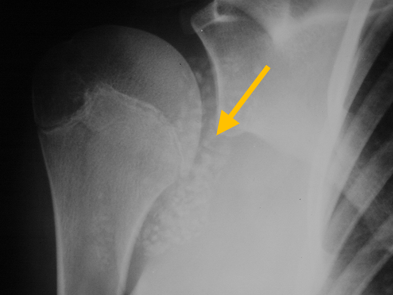

Radiographic imaging is used to help form a diagnosis. These include X-Ray, MRI, CT and Bone Scans

An example of an MRI is shown.